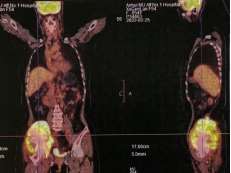

术后影像

近年来,安徽医科大学第一附属医院骨病骨肿瘤病区在胡勇教授的带领下,已完成多例3D打印定制假体重建手术,涵盖了骨盆骶骨、胫骨股骨、肩肘关节、髋膝关节等。利用个性化3D打印假体,可以做到精准化肿瘤切除和假体安装,在保证肿瘤切除边界的前提下达到骨与软组织结构的生物力学重建,最大限度保留患肢功能,极大提高了患者的生存质量,延长了患者的生存周期,是我院的特色医疗技术之一。